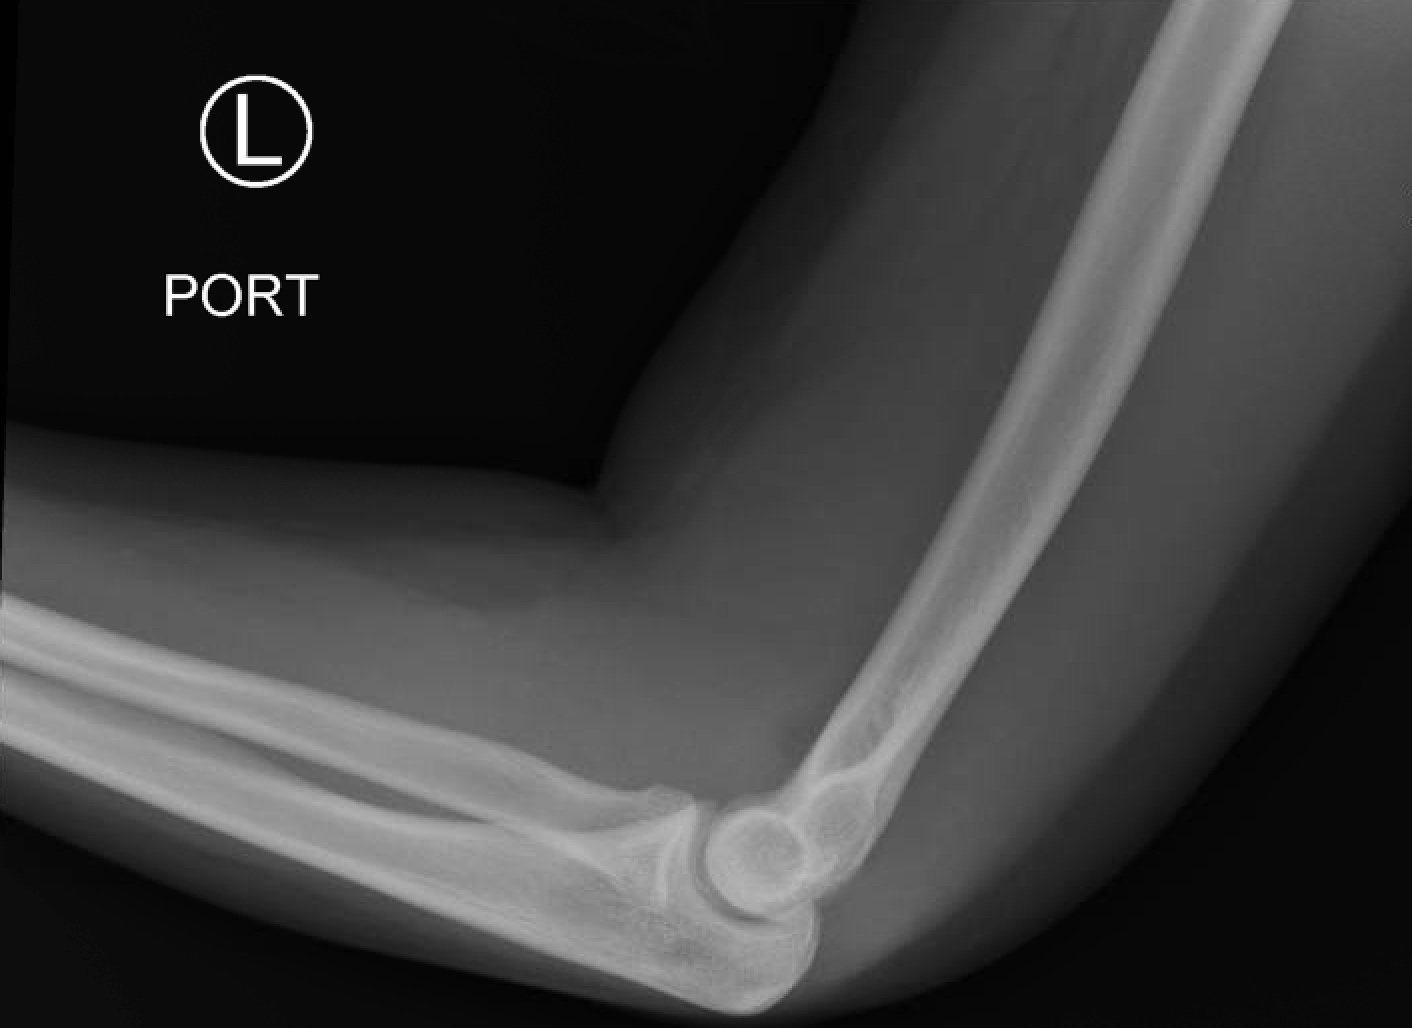

Posterior Elbow Dislocation, Lateral XRay, reduced. JETem 2016

Posterior Elbow Dislocation